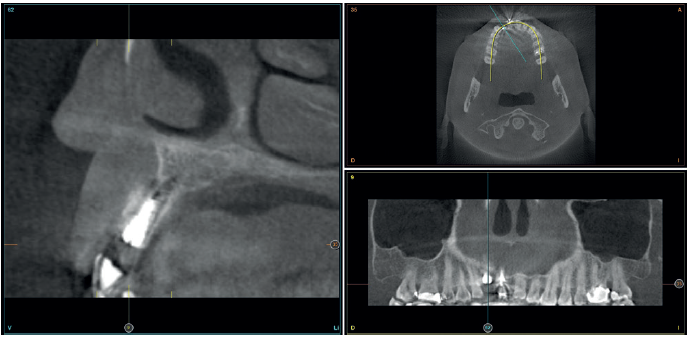

Cuatro meses después, se realiza un nuevo Cone-Beam dental para poder cuantificar la ganancia obtenida en anchura con el procedimiento regenerativo. Se observa en el corte seccional como se ha logrado una anchura de cresta de más de 7 mm y una regeneración completa del reborde alveolar, lo que permite la inserción de un nuevo implante dental en la posición adecuada (Figura 10). En la reentrada quirúrgica se constata la información del Cone-Beam con una integración total del material de injerto, tal como se muestra en las imágenes clínicas en el momento de la elevación del colgajo para la inserción del implante (Figuras 11 y 12). Se procede a la retirada del microtornillo y la colocación del implante, que se realiza mediante la compresión vestibular del injerto para ganar de esta manera aún más contorno en esta área (Figura 13). El implante se deja en una fase quirúrgica, con un pilar de cicatrización bajo que permita una localización posterior del mismo sin una cirugía agresiva del tejido blando para cuando se inicie la confección de la prótesis. El provisional sigue siendo una pieza en extensión desde el diente 1.1.